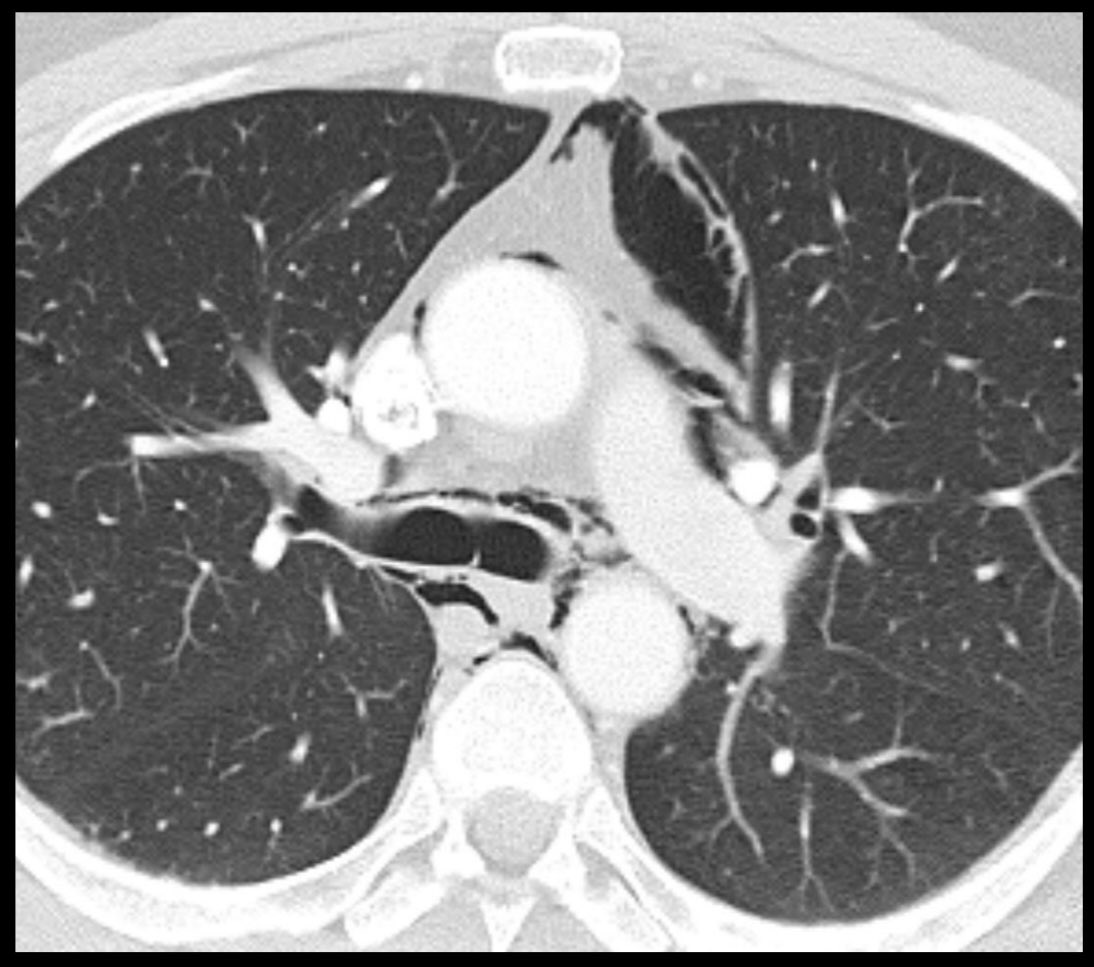

@ebtsai

Emily B. Tsai, MD

4 years

Pneumomediastinum in a scuba diver 🤿